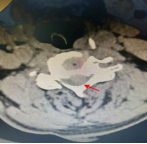

术前影像资料显示C3/C4椎间盘突出、极重度颈椎椎管狭窄、C5/6椎体融合

患者李某,70岁,因“四肢乏力、行走不稳1年,加重1个月”入住新利备用网骨科二区,入院检查诊断为:脊髓型颈椎病、颈椎椎管狭窄症(C3/C4极重度)、慢性不完全性四肢瘫。其中C3/4节段椎管占位率超过50%以上,脊髓受压极其严重,若病情继续进展,可能导致高位截瘫甚至呼吸衰竭,危及生命。且李某还存在C5、6节段先天性融合,短颈畸形,进一步增加了术中暴露和置钉的难度,对主刀医生的经验、技术及团队配合要求极高。